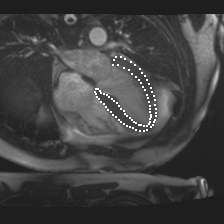

Accurate segmentation and motion estimation of myocardium have always been important in clinic field, which essentially contribute to the downstream diagnosis. However, existing methods cannot always guarantee the shape integrity for myocardium segmentation. In addition, motion estimation requires point correspondence on the myocardium region across different frames. In this paper, we propose a novel end-to-end deep statistic shape model to focus on myocardium segmentation with both shape integrity and boundary correspondence preserving. Specifically, myocardium shapes are represented by a fixed number of points, whose variations are extracted by Principal Component Analysis (PCA). Deep neural network is used to predict the transformation parameters (both affine and deformation), which are then used to warp the mean point cloud to the image domain. Furthermore, a differentiable rendering layer is introduced to incorporate mask supervision into the framework to learn more accurate point clouds. In this way, the proposed method is able to consistently produce anatomically reasonable segmentation mask without post processing. Additionally, the predicted point cloud guarantees boundary correspondence for sequential images, which contributes to the downstream tasks, such as the motion estimation of myocardium. We conduct several experiments to demonstrate the effectiveness of the proposed method on several benchmark datasets.